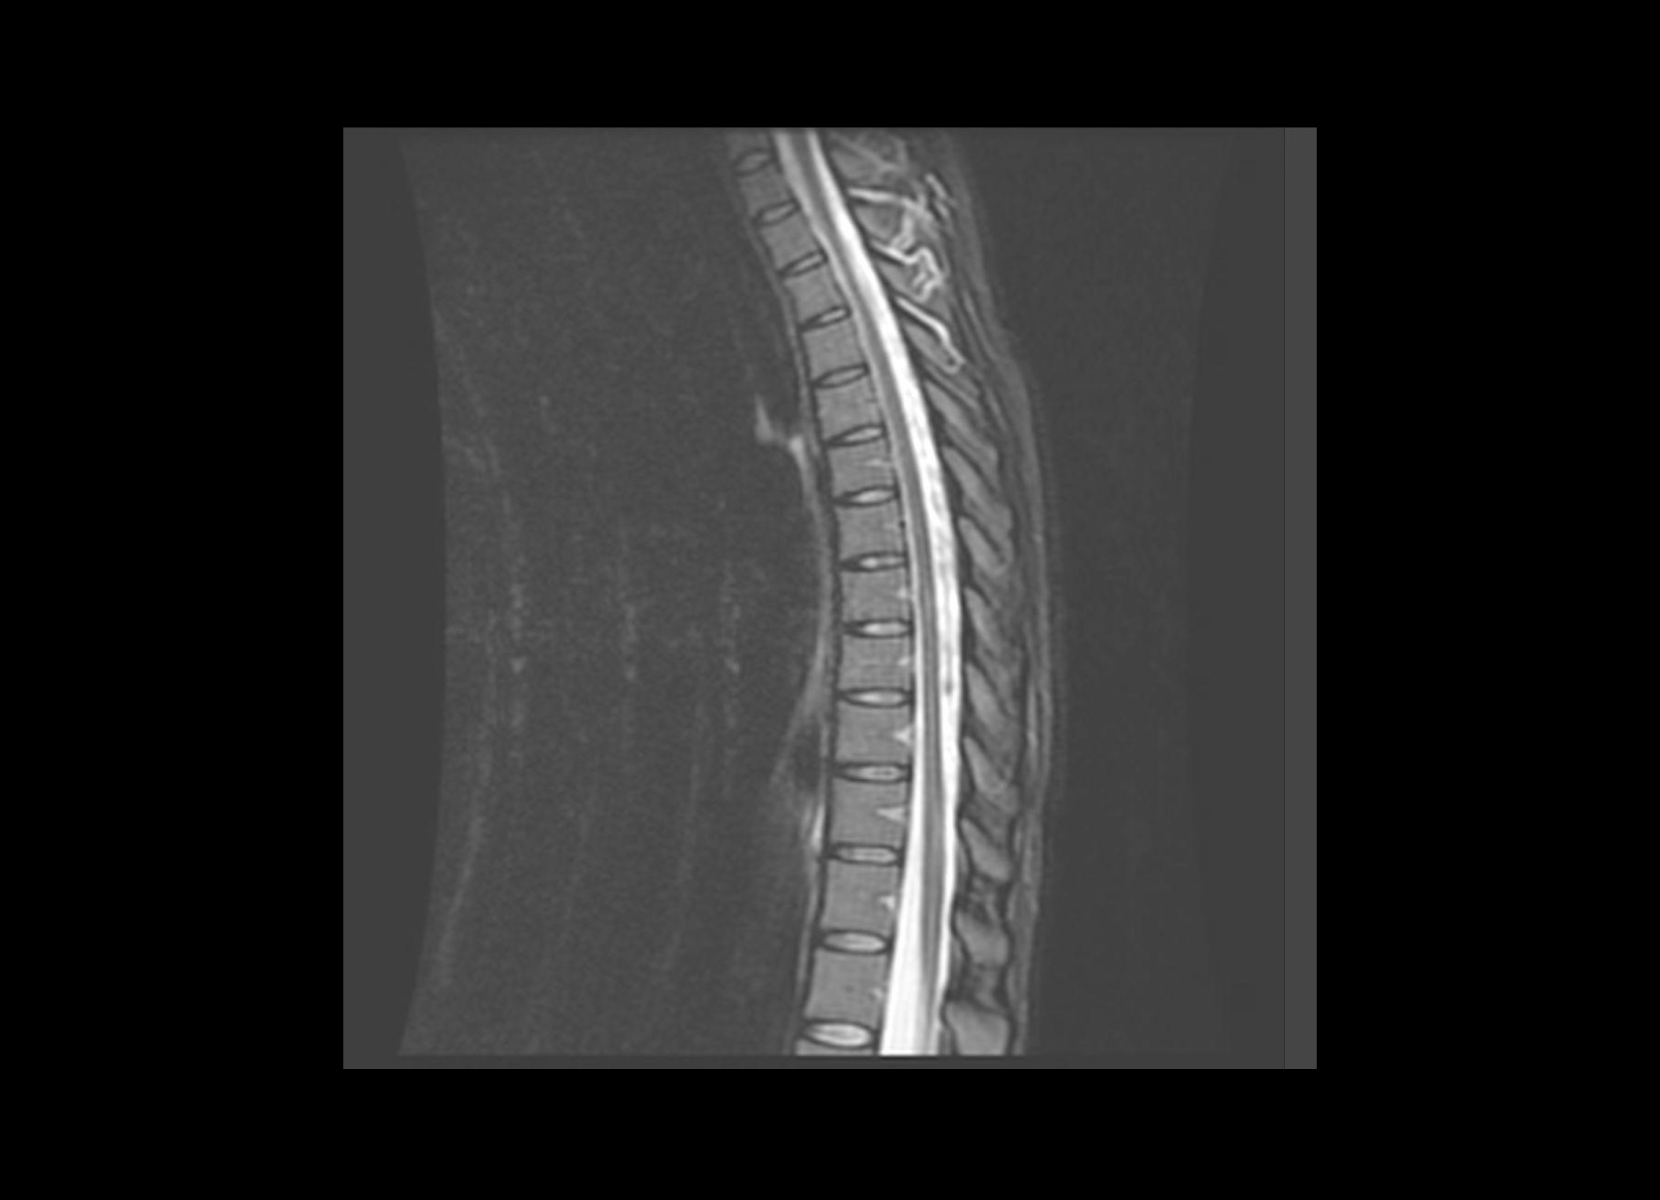

Conventional

STIR

SubtleSYNTH™

(Synthesized STIR)™

Trauma

GE 1.5T

C-spine